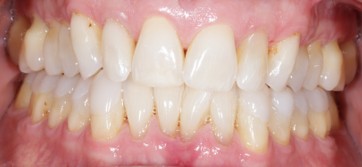

As a dentist specializing in Prosthodontics, Dr. Yepez’ philosophy has always been driven by providing excellent treatment to her patients in a caring and comfortable atmosphere, emphasizing in prevention and education. Her goal is to exceed the expectations of her patients by providing appropriate and quality care allowing them to make an educated decision about their dental treatments.